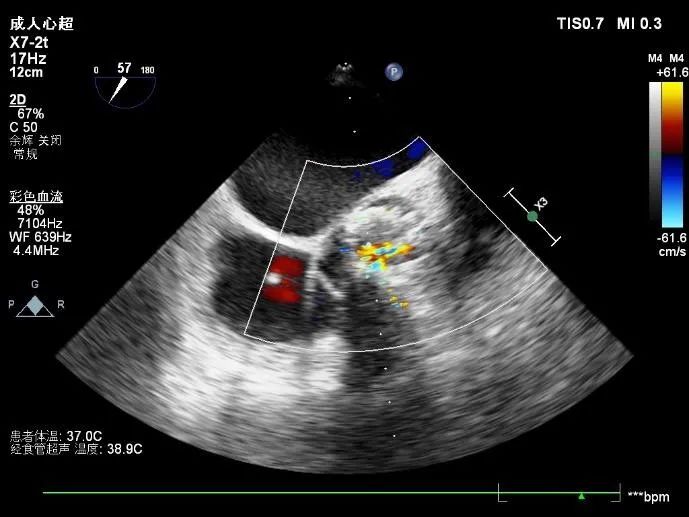

患者女性,72岁,主诉胸闷、气短,以“心力衰竭”入院,超声检查主动脉瓣Vmax=4.88m/s,PGmean=58mmHg,主动脉瓣返流彩束面积1.0cm³,诊断为重度主动脉瓣狭窄伴少量反流。

超声评估: